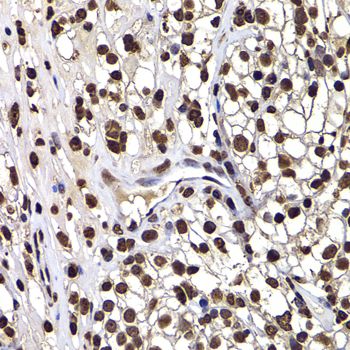

IHC-P analysis of human kidney cancer tissue using GTX33160 DNAJB6 antibody.

Dilution : 1:100